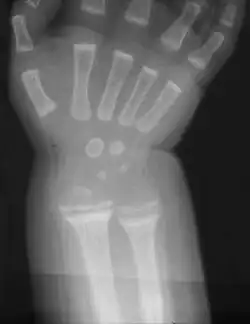

Im zweiten bis dritten Lebensmonat zeigen sich die ersten Symptome in Form von Unruhe, Schreckhaftigkeit, vermehrtem Schwitzen und dadurch ausgelöstem juckendem Hautausschlag (Miliaria). Etwa einen Monat später kommen eine Muskelschwäche mit Froschbauch, Verstopfungsneigung (Obstipation) und erste Knochenerweichungen am Schädel (Kraniotabes) hinzu. Jetzt kann der Calciummangel zusätzlich zu gesteigerter Muskelerregbarkeit (Tetanie) bis hin zu Krämpfen führen. Wiederum etwa einen Monat später entsteht durch Abflachung des Hinterkopfes und Auftreibung der Schädelnähte (Epiphytenbildung) das Bild eines Quadratschädels. Die perlschnurartig aufgereihten Auftreibungen der Knorpel-Knochen-Grenzen an den Wachstumsfugen der Rippen am Brustkorb wird auch Rosenkranz genannt. Auch Hand- und Fußgelenke verbreitern sich durch Auftreibung der Epiphysen zunehmend (Marfan-Zeichen, „doppelte Glieder“). Später zeigen sich ein verzögerter Zahndurchbruch, Defekte im Zahnschmelz, eine verzögerte Mineralisation der Kieferknochen bis hin zum offenen Biss. Weil der Brustkorb ungewöhnlich weich ist, führt der Muskelzug am Zwerchfellansatz zu einer Einziehung, der Harrison-Furche. Zu den weiteren typischen Knochenverformungen gehören Beinverkrümmungen (O-Beine, Genua vara), wobei die langen Röhrenknochen varisch (nach innen) verbogen sind, und die Fehlstellungen weniger im Gelenk selbst liegen. Bei Erwachsenen sind die Wachstumsfugen schon verschlossen und es kommt bei einem Vitamin-D-Mangel lediglich zu einer Osteomalazie ohne die im Kindesalter so typischen Knochenverformungen.

Die Diagnose wird durch die typischen Symptome, die im Röntgenbild sichtbaren Veränderungen an den Knochen sowie durch eine erhöhte Aktivität der Alkalischen Phosphatase im Blut gestellt.[6] Da die Röntgenuntersuchung keine spezifischen Unterscheidungsmerkmale zwischen einer Calciummangel- und einer Phosphatmangel-Rachitis zeigt, muss zwischen diesen Formen durch weitere Laboruntersuchungen unterschieden werden. Hierzu dient eine Bestimmung des Parathormons, das bei calcipenischer Rachitis erhöht und bei der phosphopenischen Form normal ist. Weiterhin wird die Konzentration der einzelnen Vitamin-D-Vorstufen bestimmt um eine klassische Vitamin-D-Mangel-Rachitis (mit erniedrigten 25(OH)Vitamin-D3-, aber niedrig normalen Dihydroxy-Cholecalciferol-Werten) von den Vitamin-D-abhängigen Formen (mit normaler 25(OH)Vitamin-D3- und abnorm niedriger Dihydroxy-Cholecalciferol-Konzentration bei der VDAR I beziehungsweise normaler Vitamin-D3- und exzessiv hoher Dihydroxy-Cholecalciferol-Konzentration bei der VDAR II) abzugrenzen.